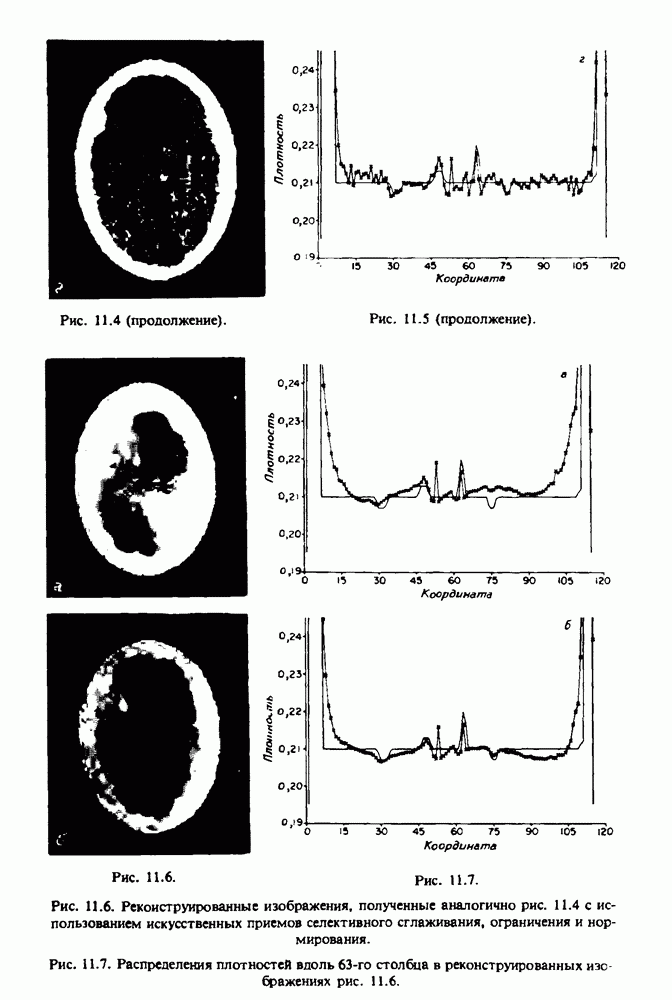

Для формирования трехмерного изображения системы желудочков (рис. 15.7) были использованы все рассмотренные в трех предыдущих разделах операции определения границ органов, исключения скрытых их частей поверхности и наложения теней. Число зарегистрированных граничных граней для системы желудочков составляло 8970, при этом регистрация множества из 80 х 80 х 38 элементарных объемов требует менее 0,5 мин машинного времени (на мини-ЭВМ типа Eclipse S/200).

Последующие иллюстрации относятся к отображению области спинного мозга пациента, страдающего дисрафизмом (напомним, что дисрафизм — это заболевание, при котором спинной мозг развивается ненормально). На рис. 15.8 представлено реконструированное изображение поперечного сечения тела пациента, на котором хорошо видна костная спи-кула, разделяющая позвоночный столб.

На рис. 15.8 нами выделена область, состоящая из элементов

Рис. 15.8. (см. скан) Поперечное сечение тела пациента, страдающего дисрафизмом. Костная спикула показана стрелкой. Рамкой обведена область, состоящая из элементарных объемов и содержащая изображение спинного мозга.

изображения и содержащая изображение ствола спинного мозга. Каждая из ячеек имеет размеры 0,8 х 0,8 мм. Из серии восьми смежных срезов толщиной 1,5 мм методом линейной интерполяции формировался трехмерный массив усредненных плотностей, состоящий из элементарных объемов размером 0,8 х 0,8 х 0,8 мм. Был точно установлен такой диапазон чисел Хаунсфилда, чтобы элементарные объемы от кости и окружающих тканей можно было различить, и в результате получены изображения двух последовательных слоев (рис. 15.9), содержащих элементарных объемов.